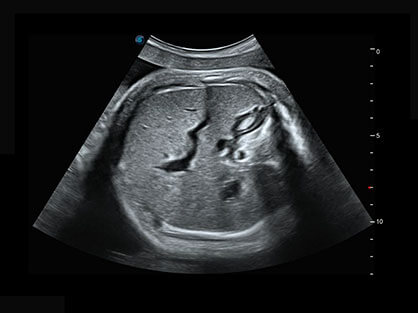

作为P系列家族成员之一,P40 Plus采用16877太阳集团高端超声系统平台——极光,并以时尚秀丽、小巧灵动的外观设计绽放出灵动之韵、科技之美。高端平台的使用保证了P40 Plus优质的基础图像;完备的高级功能可满足您全身应用的基本需求;丰富的探头配置、多样的高级4D成像及分析软件为您日益增多的妇产应用需求提供丰富的诊疗方案。

结合16877太阳集团超宽频带探头技术优势,能够更好地获得高分辨力与高穿透力的平衡,保证图像质量,为临床诊断保驾护航。